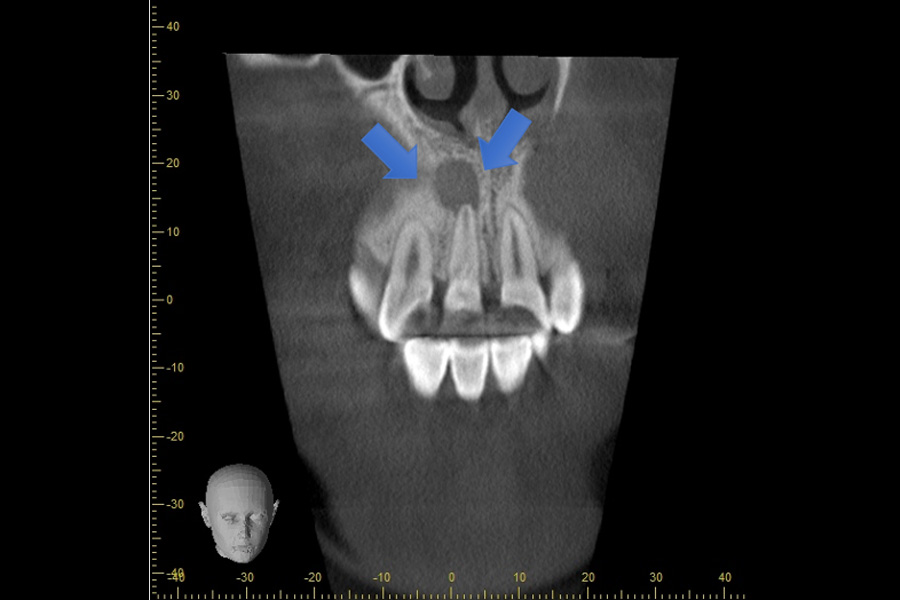

| 治療内容 | CTにて根尖病巣(幅5mm×7mm)が確認できる |

| 治療のリスク | 隣在歯(右上前から2番目)の根の先にまで病巣が近接しているため術後神経血管の循環が失われて神経が痛んでくる可能性があります。 |

| 治療内容 | 歯根端切除 MTAセメントによる逆根管充填 他院で根管治療を複数回行っていたが痛みが引かない為に来院された方です。 コンビームCTにて精査したところ、根尖部に大きな透過像を認めました。 |